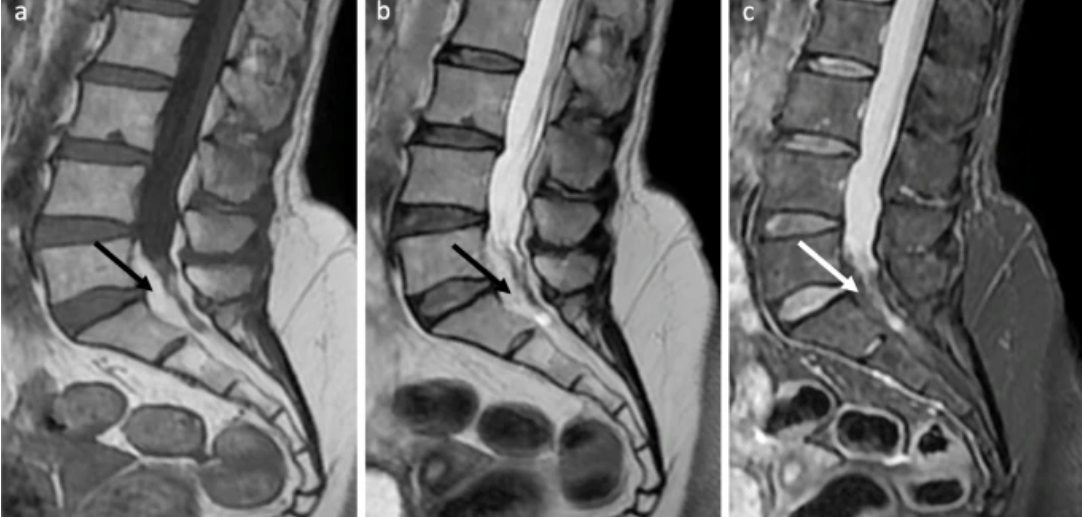

Image Type Lumbar Spine X-Ray CT Scan MRI Scan Anteroposterior (AP) Canal Diameter Cauda Equina Nerve Root Area Conus Medullaris Level Cross-Sectional Area (CSA) of Spinal Canal Disc-Height Index (DHI) Disc Herniation Size Disc Herniation Types Dural Sac CSA Epidural Fat Thickness Filum Terminale Thickness Foraminal Height and Width High-intensity Zone (HIZ) Lateral Recess Width/Depth Modic Endplate Changes (Type I, II, III) Modic (Marrow Signal) Changes Pfirrmann Classification (I-V) Vertebral Bone Quality (VBQ) Score Vertebral Endplate Defects